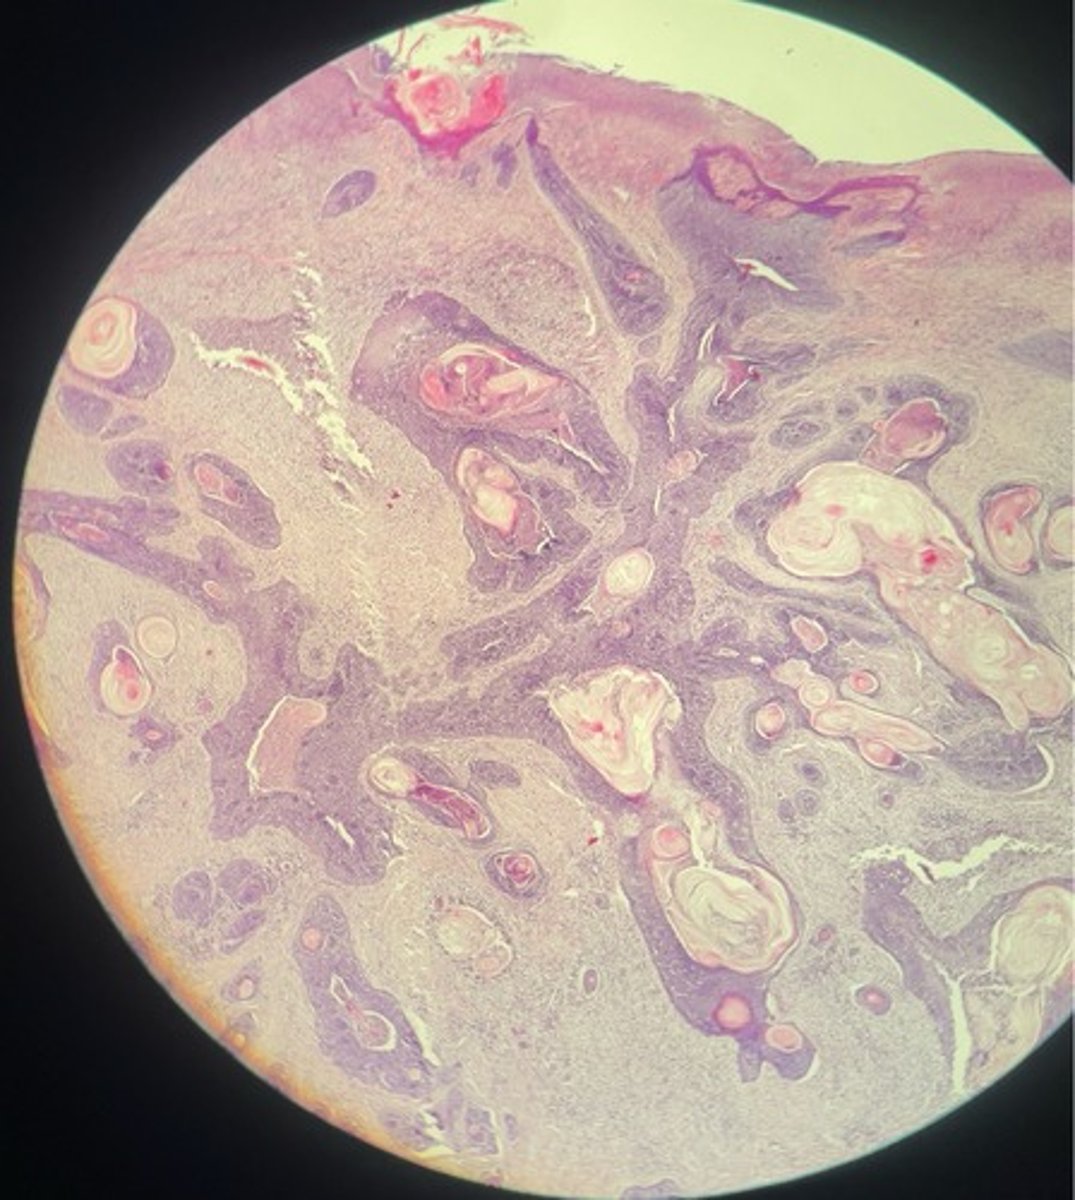

Squamous cell carcinoma => malignant epithelial neoplasm

- irregular masses + cords proliferating downwards

- ulcerations on surface

- keratin pearls

- coag. necrosis

- mitotic figures + neoplastic cells